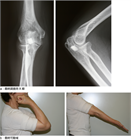

1. 直達外力による肘頭骨折と上腕三頭筋の牽引力によって起こる肘頭剝離骨折がある。

前者に対しては観血整復内固定術が行われることが多く、tension band wiring、intramedullary screw fixation、肘頭用アナトミカルロッキングプレートによるプレート骨接合術などの選択肢がある。